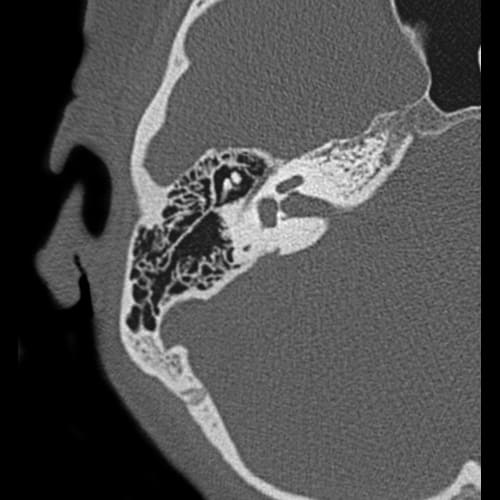

Височные кости